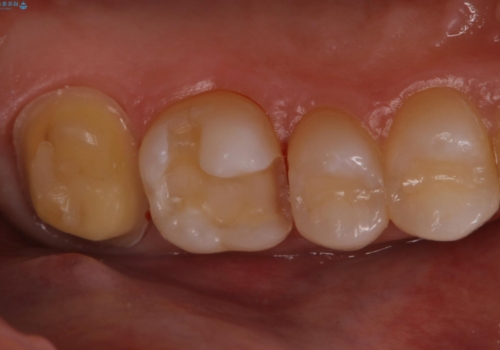

金属を除去し、虫歯の治療後に型取りを行い、清掃性、審美性に優れたセラミックインレー、セラミッククラウンを装着いたしました。

新しい被せ物が入った後は、歯肉の腫れはなくなり、定期検診の際もプラーク等の貯留もみられなくなりました。